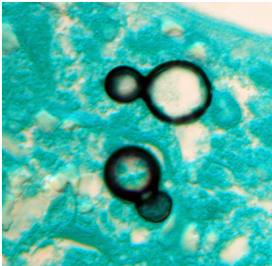

The study, led by scientists at the universities of Manchester in the UK, Amsterdam, and the Westerdijk Institute in the Netherlands, showed that most fungal pathogens identified by the World Health Organisation (WHO) are either already resistant or rapidly acquiring resistance to antifungal drugs.

Aspergillus, Candida, Nakaseomyces glabratus, and Trichophyton indotineae are the major fungicide resistant infections. These can have devastating health impacts on the elderly and people with weak immune systems.

Dr. Norman van Rhijn from The University of Manchester said that invasive fungal diseases have been responsible for many drug resistance problems over the past decades.

van Rhijn explained that “the close similarities between fungal and human cells make it hard to find treatments that selectively inhibit fungi with minimal toxicity to patients”.